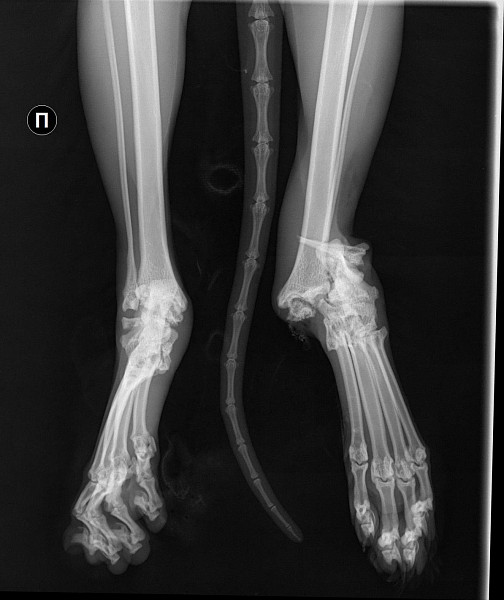

Рентген Задней Лапы Кошки: Нормы и Диагностика